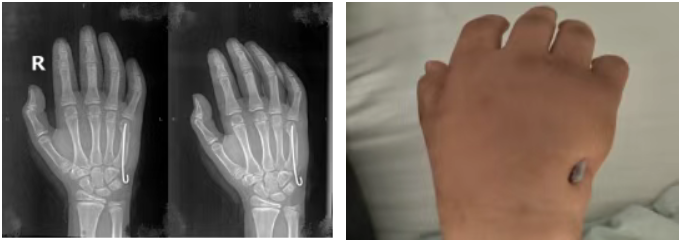

经术前讨论及与家属沟通,团队决定采用微创髓内针固定术。手术在C臂机透视下完成,闭合复位后经皮打入弹性克氏针固定,未损伤肌腱血管神经,保留骨折端血运。

手术前:

手术后:

手术顺利,未用止血带、出血量极少,术后仅留针孔大小瘢痕。患者恢复良好,术后三天返校,对效果满意。后续骨折愈合后,门诊即可抽出克氏针恢复手部功能。